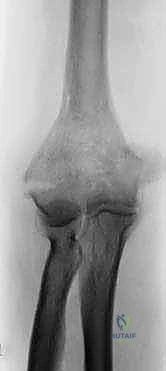

1. الأشعة السينية (X-rays): من زوايا متعددة لتحديد موقع الكسر المبدئي.

2. الأشعة المقطعية ثلاثية الأبعاد (3D CT Scan): وهي خطوة لا غنى عنها في حالات الكسور المفتتة. تساعد هذه الأشعة الدكتور هطيف في بناء خريطة جراحية دقيقة، لمعرفة حجم الشظايا العظمية، وتحديد ما إذا كان العظم قادراً على تحمل المسامير أم أن استبدال المفصل هو الخيار الأوحد.

الصور الشعاعية الإضافية والنتائج داخل غرفة العمليات

يحرص الأستاذ الدكتور محمد هطيف على التوثيق الشعاعي الدقيق أثناء وبعد العملية للتأكد من الموضع المثالي للمفصل.